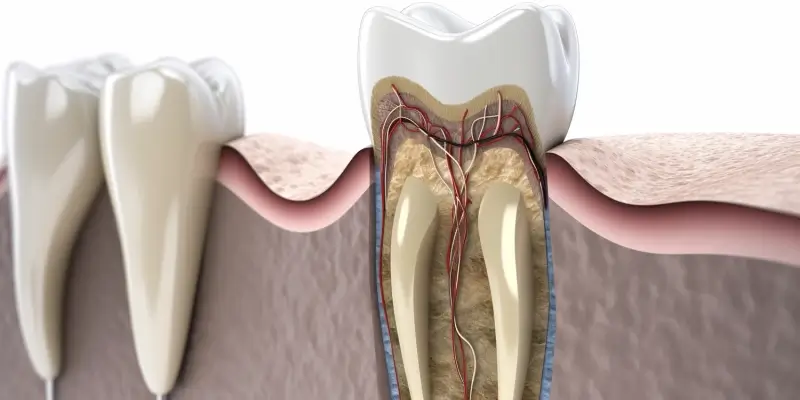

Podczas wizyty u dentysty można spodziewać się różnych zabiegów, które mają na celu poprawę zdrowia jamy ustnej. Najczęściej wykonywanym zabiegiem jest profesjonalne czyszczenie zębów, które polega na usunięciu kamienia nazębnego oraz osadów płytki bakteryjnej. Taki zabieg nie tylko poprawia estetykę uśmiechu, ale także zapobiega chorobom dziąseł i próchnicy. Innym popularnym zabiegiem jest fluoryzacja, która polega na nałożeniu specjalnego preparatu zawierającego fluor na powierzchnię zębów w celu ich wzmocnienia i ochrony przed próchnicą. W przypadku wystąpienia próchnicy dentysta może zalecić wypełnienie ubytku materiałem kompozytowym lub amalgamatowym. W bardziej skomplikowanych przypadkach konieczne może być leczenie kanałowe, które ratuje ząb przed ekstrakcją poprzez usunięcie chorej miazgi zęba. Dentysta może także zaproponować wybielanie zębów lub zakładanie koron protetycznych w przypadku znacznego uszkodzenia zęba.